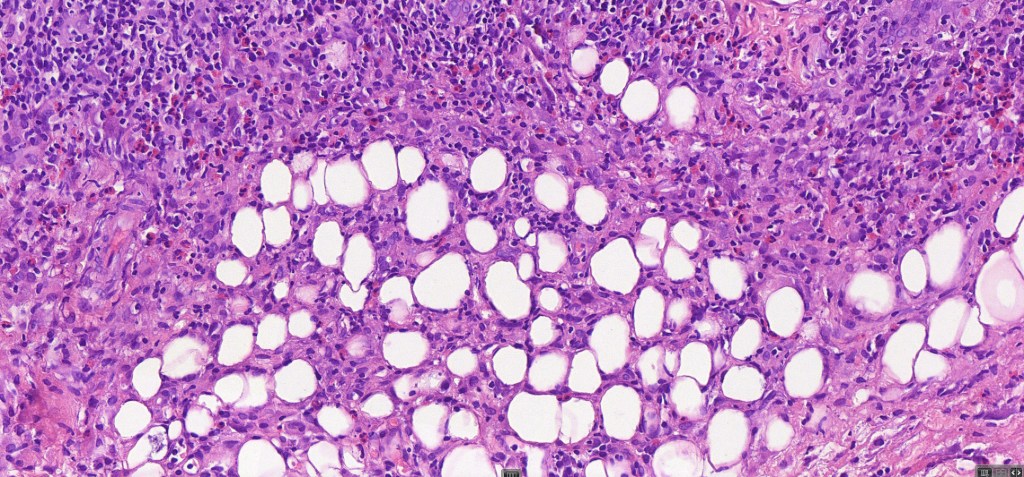

Histological features

•Type A: 75-80%, wedge shaped infiltrate with base uppermost, large, anaplastic cells with abundant cytoplasm and vesicular nuclei containing prominent nucleoli, can resemble Reed-Sternberg cells, conspicuous mitoses & background infiltrate of lymphocytes, plasma cells, histiocytes, neutrophils & eosinophils

•Variable epidermal necrosis, epidermotropism, edema, hemorrhage & vasculitis/thrombosis